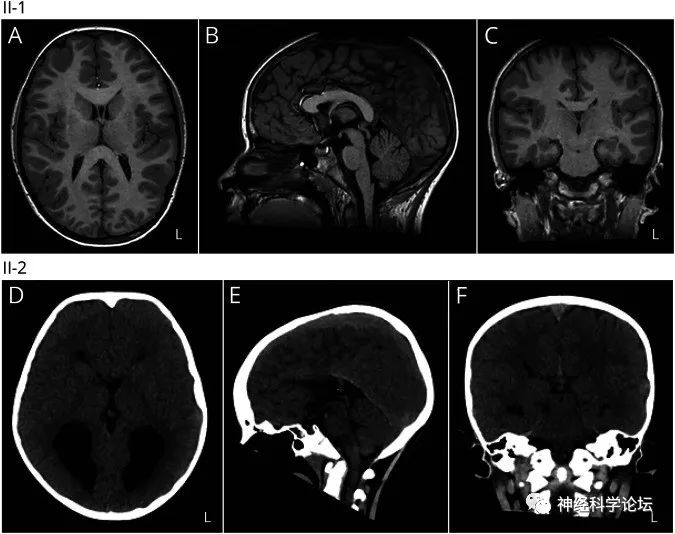

大部分患者头MRI正常,但一些DCC基因杂合致病突变的患者可表现胼胝体部分或完全发育不良。

与先天性镜像运动相关的脑畸形有:父亲和女儿的胼胝体发育不良伴DCC杂合子p.Met1*突变;TUBB3杂合子p.Thr312Met突变的母亲和儿子的胼胝体发育不良、脑回障碍和畸形蚓部;TUBB基因p.Arg121Trp杂合子突变的一个父亲和两个女儿的胼胝体发育不良、脑回运动障碍、蚓部异常和脑室不对称;TUBA1A中p.Glu155Asp杂合子突变患者的胼胝体发育不良、脑回障碍、基底神经节畸形和蚓部异常;POMGNT1中p.Pro312Leu纯合子突变患者的脑积水、发育不全的胼胝体、多微回和小脑囊肿。

CMM的诊断是有相关症状的先证者,经基因鉴定发现DCC、NTN1或RAD51的杂合致病突变。具有镜像运动持续存在于整个成年期,缺乏其他提示某种综合征的临床证据和后续的神经系统发现的临床特征、头颅MRI正常或者存在胼胝体部分或完全发育不良的影像发现以及家族史的个体要怀疑CMM。